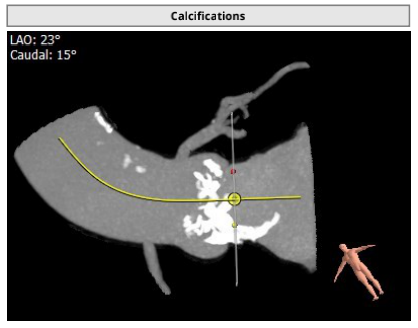

2021年12月17日,四川省人民医院结构性心脏病团队成功挑战高龄主动脉瓣严重狭窄合并弥漫钙化,顺利完成SAPIEN 3瓣膜植入。在团队成员紧密配合下,克服患者入路狭小弥漫钙化病变,充分利用SAPIEN 3瓣膜的优异性能,顺畅完成过弓、跨瓣及释放操作,手术取得圆满成功。这也是四川省人民医院首例应用SAPIEN 3瓣膜完成的TAVR手术。